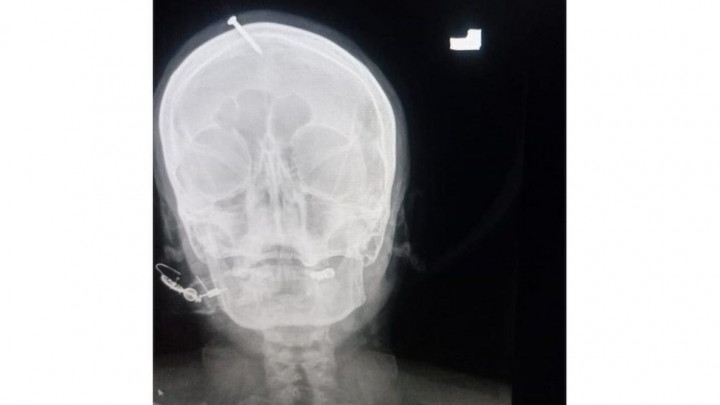

Pakistan Buru Dukun yang Tancapkan Paku ke Kepala Perempuan Hamil